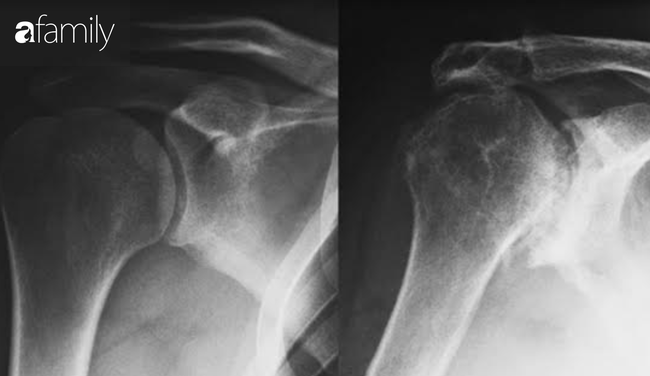

Sau khi thăm khám, bác sĩ chẩn đoán ông L. bị rách sụn viền vai, trật khớp cùng đòn bên phải và chỉ định phẫu thuật nội soi để phục hồi chức năng của vai.

Nếu không được điều trị đúng cách, chấn thương khớp vai có thể dẫn đến thoái hoá khớp, bại liệt cánh tay, vôi hóa, ảnh hưởng nặng nề tới hoạt động thường ngày.

Đến khi người bệnh cảm thấy cơn đau ngày càng nặng đến mức không ngủ được, bị hạn chế trong sinh hoạt hằng ngày mới đến bệnh viện thì vị trí chấn thương đã ở giai đoạn tiến triển, gây ra những biến chứng như gai xương, viêm xương khớp thoái hóa, cứng khớp, co rút khớp…